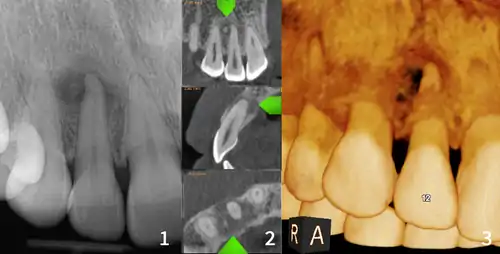

| Florid osseous dysplasia of the mandible | |

| Diagnostic method | X-ray, CBCT scan, vitality testing of teeth |

Cemento-osseous dysplasia (COD) is a benign condition of the jaws that may arise from the fibroblasts of the periodontal ligaments. It is most common in African-American females. The three types are periapical cemental dysplasia (common in those of African descent), focal cemento-osseous dysplasia (Caucasians), and florid cemento-osseous dysplasia (African descent). Periapical occurs most commonly in the mandibular anterior teeth while focal appears predominantly in the mandibular posterior teeth and florid in both maxilla and mandible in multiple quadrants.

Diagnosis is important so that the treating doctor does not confuse it for another periapical disease such as rarefying osteitis or condensing osteitis. Incorrect diagnosis could lead to unnecessary root canal treatments. It can be diagnosed by radiographic appearance. Confirming the tooth is vital, as is noting the demographic (African American females).[1][2][3]